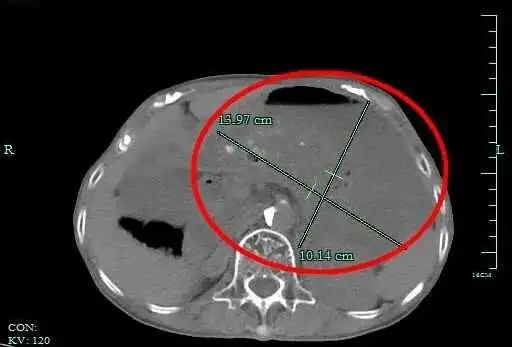

就这样吃了一个双休日,小丽嗅觉胃异常胀,上腹部还隐晦孤寂。难堪得不能,小丽在家东谈主追随下,来到杭州市一集团瓶窑院区(余杭三院)就诊。消化内科孙国明医师接诊后,搜检发现,小丽的胃里有大批莫得消化的食品,胃腔比空心景色扩大近40倍。

临了,小丽被会诊为“急性胃扩张”,入院诊治。所幸,经诊治后,小丽腹痛症状得以缓解,莫得形成其他严重末端。